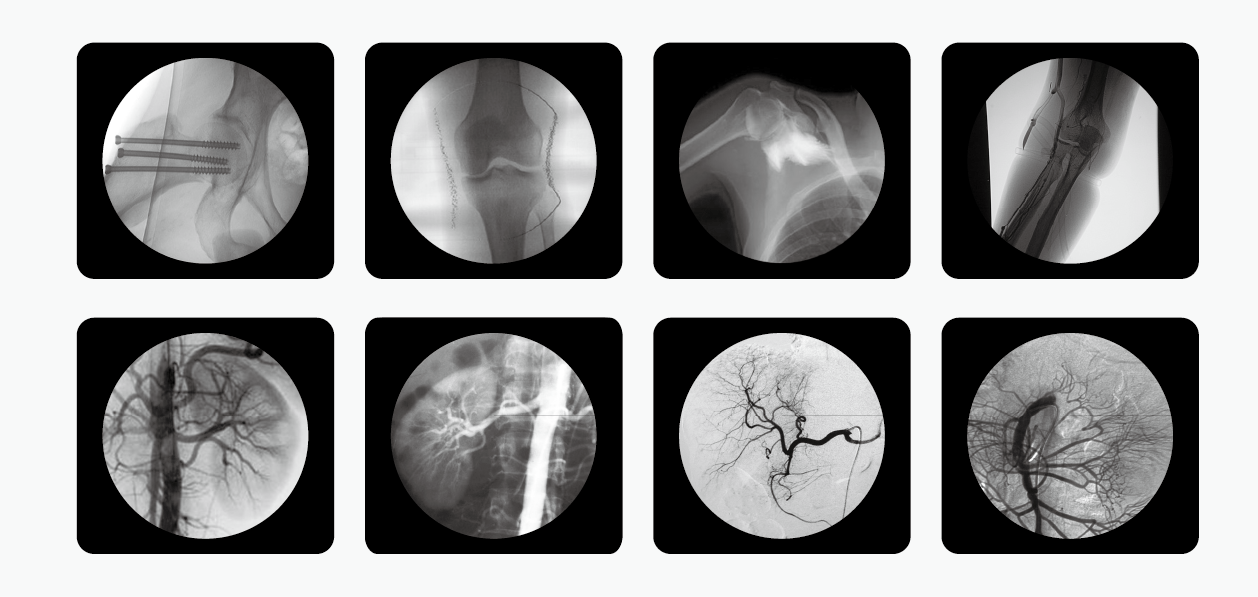

C型臂也就是我們所說的C臂機(jī)或C形臂X光機(jī)等,因?yàn)槠洫?dú)有的C型的機(jī)架而被這么命名,儀器主要由產(chǎn)生X射線的球管,采集圖像的影像增強(qiáng)器和CCD攝像機(jī),以及圖像處理的工作站組成,是現(xiàn)代臨床不可或缺的醫(yī)療輔助設(shè)備。

南京普愛醫(yī)療C形臂X光機(jī)是國內(nèi)眾多生產(chǎn)廠家中的一匹黑馬,該公司擁有多種型號(hào)的C形臂X光機(jī),其中PLX7000C被廣泛應(yīng)用于介入科、骨科、外科、矯形外科、泌尿外科、脊柱外科、腹部外科、疼痛科、心臟科、消化科、婦科及手術(shù)室等。

擁有更大功率的高壓發(fā)生器適合對肥胖病人的高密度組織進(jìn)行成像,并且也有更高熱容量的球館可以滿足長時(shí)間、大量手術(shù)的需要。多種工作模式,滿足各種臨床需要,多葉與垂直光影控制,有效減少軟X線,大幅降低皮膚劑量,其還配有進(jìn)口品牌影像增強(qiáng)器,全數(shù)字化CCD攝像機(jī),提供高分辨的優(yōu)質(zhì)圖像。